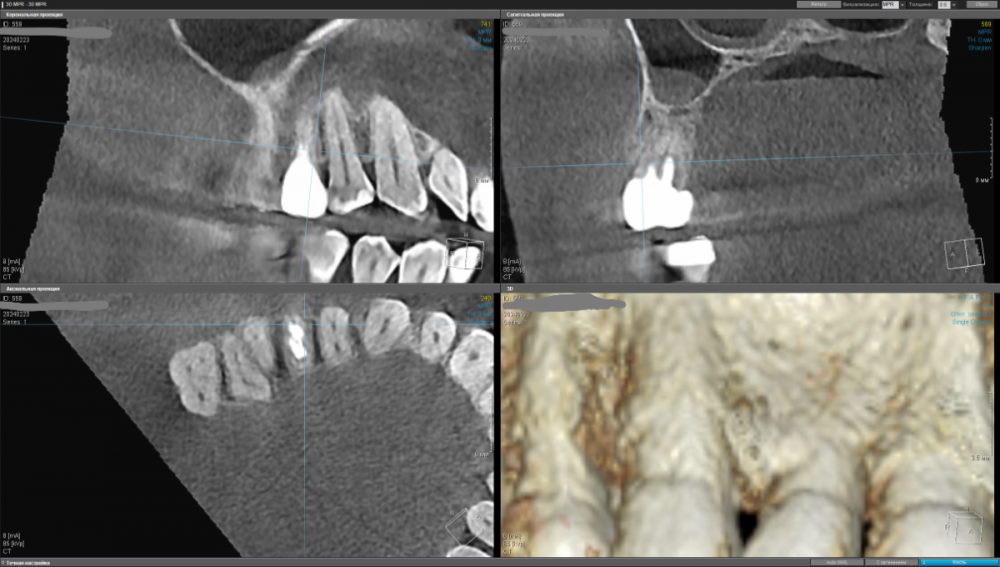

kamacho Опубликовано 24 февраля, 2024 Автор Поделиться Опубликовано 24 февраля, 2024 Попробую привлечь ваше внимание дополнительными снимками. Вопросы которые я себе задаю когда смотрю на КТ: 1) Между 14 и 15 зубом, это убыль фуркации или артефакт при съемке кт ? 2) В районе 37 ого зуба это артефакт или кариес ? Я пытаюсь санировать ротовую полость уже наверное лет пять, и никогда не удается решить проблему. Прошел множество клинник (наверное штук 5-6, включая 1 зарубежную). Но после попыток лечения, возникает одна и таже проблема, как только начинаю добавлять углеводы(не сладости) в рацион, какой-то очаг инфекции дает о себе знать. Буду очень признателен если поможете советом или догадкой. Ссылка на комментарий

Carioznik Опубликовано 25 февраля, 2024 Поделиться Опубликовано 25 февраля, 2024 15.02.2024 в 18:43, kamacho сказал: есть ли показания для лечения этого зубика? По идее есть, но нужно разбираться 15.02.2024 в 18:43, kamacho сказал: Могут ли не до конца пролеченные корни вызывать такую симптоматику ? Нет 17 часов назад, kamacho сказал: Между 14 и 15 зубом, это убыль фуркации Нет. Похоже, что на 14 есть кариес. Возможно это и причина кровоточивости и запаха. Но нужно смотреть настоящую КТ , а не скрины. 18 часов назад, kamacho сказал: районе 37 ого зуба это артефакт или кариес ? Больше на артефакт похоже, но это не точно: нужно смотреть настоящую КТ , а не скрины 1 Ссылка на комментарий